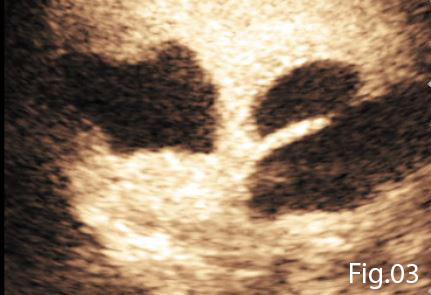

A Bolus of 2.4ml of SonoVue (Bracco, Milan) was administered through a cannula situated in the left antecubital fossa, followed by a 10ml bolus of saline solution. Both abscesses demonstrated peripheral enhancement with no uptake seen in the central fluid components (Figure 3). On further evaluation of the anterior gallbladder wall CEUS demonstrated a well-defined avascular defect providing a communication of the gallbladder contents with the adjacent hepatic abscess (Figure 4). These findings were conclusive of gallbladder wall perforation. A subsequent Computed Tomography confirmed this gallbladder perforation and hepatic abscess formation within segments V and V/VIII of the liver.